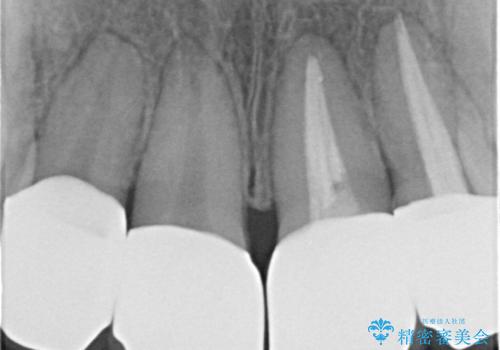

- 神経の死んでしまっている前歯の変色の改善を求めて来院されました。

根管治療をしたのち時間が経過して変色が目立つ歯と、レジン充填が複数箇所に及んでいる歯も同時にオールセラミック治療を行っていくこととなりました。

- 52.8万円(ジルコニアクラウン×4・仮歯×4)費用は治療当時の料金となります